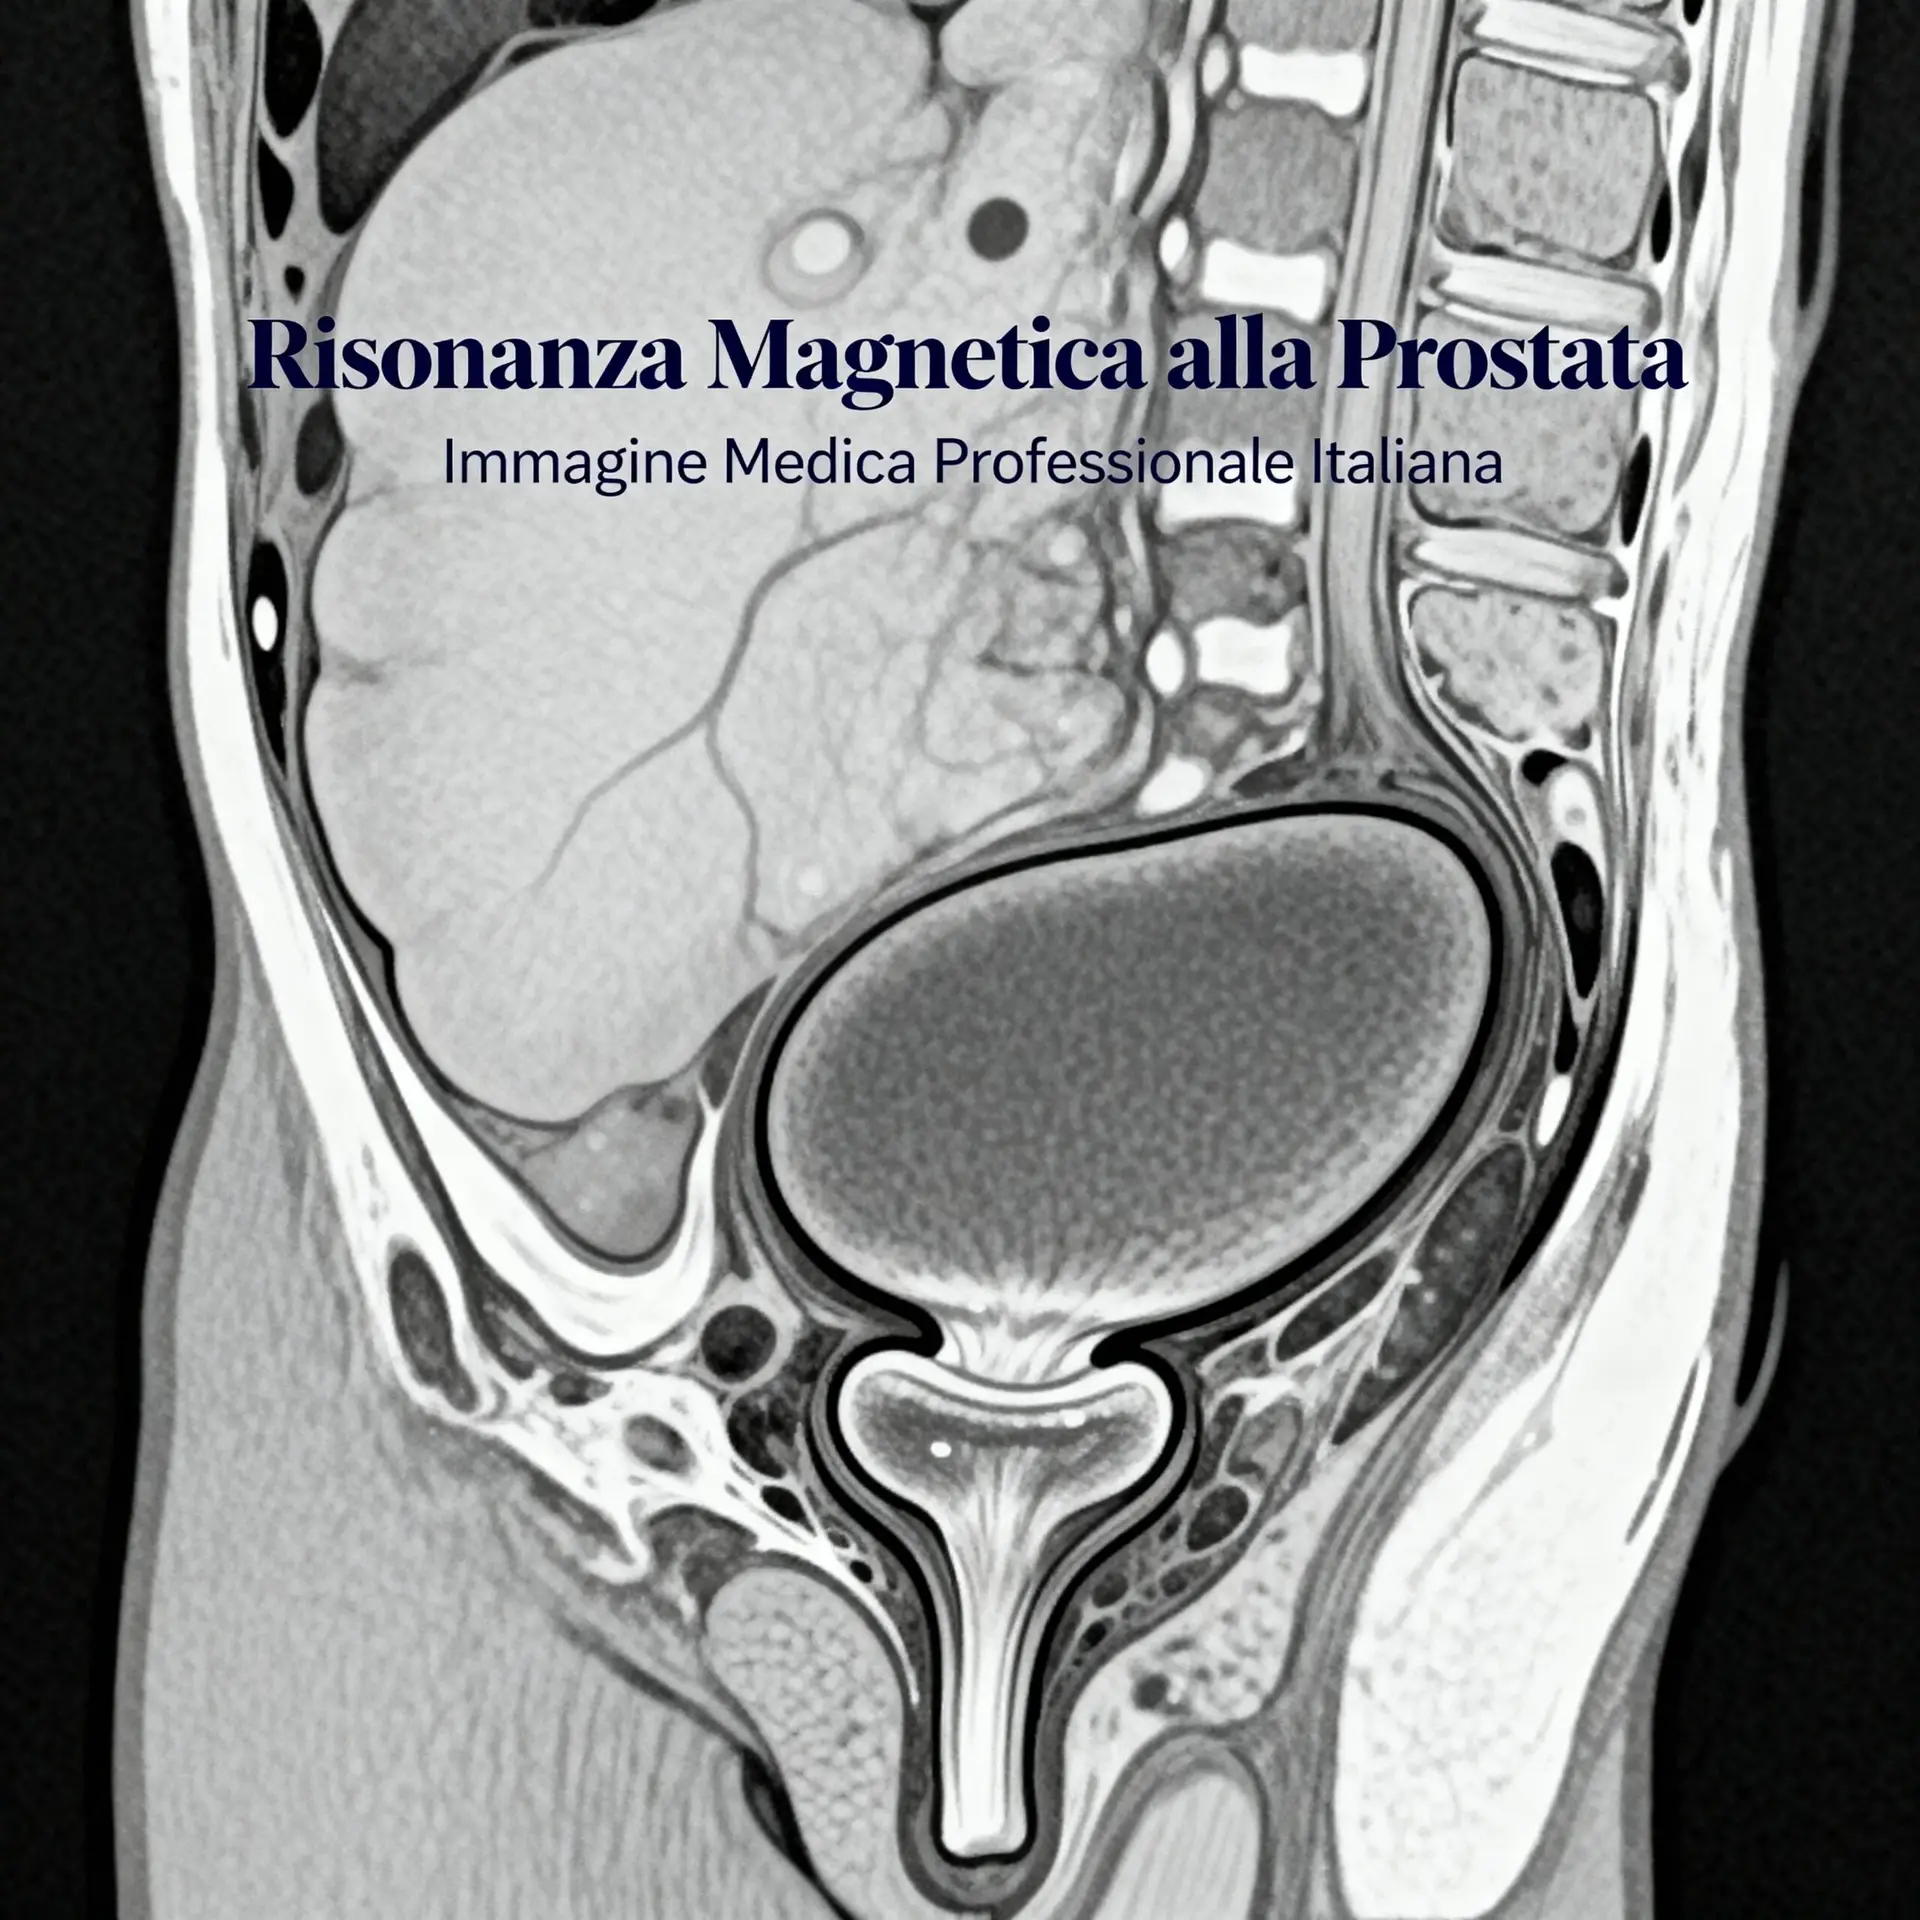

Quando parliamo di risonanza magnetica alla prostata, ci riferiamo quasi sempre alla sua forma più avanzata: la Risonanza Magnetica Multiparametrica (RMMp). Questo non è un dettaglio secondario, ma il cuore della sua efficacia. A differenza di una risonanza standard, che fornisce un’immagine puramente anatomica, la RMMp combina diverse “lenti” di osservazione per ottenere informazioni funzionali e strutturali dettagliatissime della ghiandola prostatica. È come passare da una foto in bianco e nero a un film in 4K.

L’esame utilizza un campo magnetico e onde radio, senza l’uso di radiazioni ionizzanti. La parte “multiparametrica” deriva dalla combinazione di tre sequenze principali. La prima, la T2-pesata, offre un’altissima risoluzione anatomica, mostrando con chiarezza la zona periferica e quella di transizione della prostata. La seconda, la diffusione (DWI), valuta il movimento delle molecole d’acqua nei tessuti, indicando le aree dove la densità cellulare è maggiore (tipica dei tumori aggressivi). La terza, la perfusione (DCE), studia il modo in cui il mezzo di contrasto (generalmente gadolinio) viene assorbito e rilasciato dai tessuti. Le lesioni maligne, avendo una vascolarizzazione alterata, mostrano un pattern di captazione del contrasto diverso dai tessuti sani. L’integrazione di queste tre prospettive (anatomia, densità cellulare e vascolarizzazione) permette al radiologo di classificare le lesioni con il sistema standardizzato PI-RADS (Prostate Imaging Reporting and Data System).